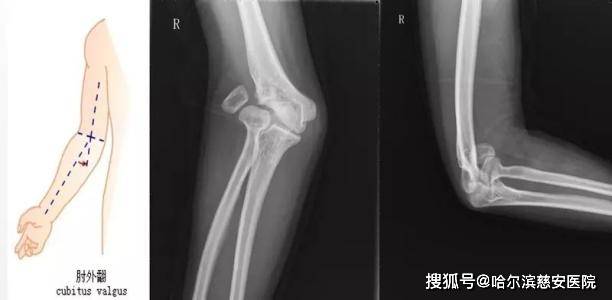

肘外翻20度兵检过了,一个关于健康与标准的探讨,健康与标准探讨,肘外翻20度如何通过兵检?

摘要:关于肘外翻20度的情况在兵检中被接受,引发关于健康与标准的讨论。这一事件提醒人们,健康标准并非一成不变,可能受到多种因素影响。肘外翻20度者成功过检,也反映出对个体差异的包容性和健康评估的多元性。这一案例引发社...